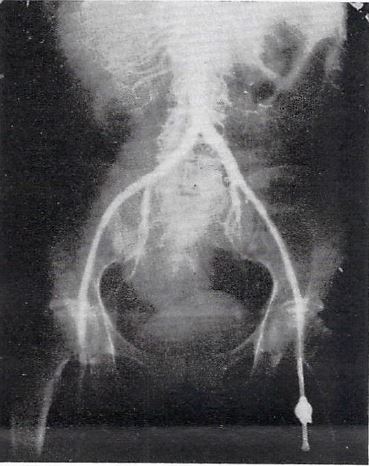

背部の盲目的直接穿刺による大動脈造影

1929年,ポルトガルの外科医・泌尿器科医Raynaldo dos Santosは,同郷のMonizがその2年前に開発した脳血管造影に触発されて,初の大動脈造影を行なった(A. Med. Contemp. 47:93-97,1929).ここに紹介するのは,このスペイン語論文発表の翌月に仏のパリ外科学会で行なわれた口演記録を掲載した同学会誌の論文である.原論文とほぼ同じ内容にやや肉付けした内容で,パリ外科学会のGossetがdos Santosの発表を紹介するという形で,そのオリジナル論文の内容を伝えるとともに,学会幹部のコメントが追加されている.

dos Santosは,内臓神経ブロックに際して偶然誤って大動脈を穿刺した場合に特に合併症がないことにヒントを得て,大動脈の直接穿刺による大動脈造影を行なった.Th12~L3高位で背部傍正中を盲目的に穿刺するもので,造影剤には100%ヨウ化ナトリウムを使用している.多少の疼痛を除けば事故はなかったとしている.論文の後に追加されているパリ外科学会幹部のコメントは非常に厳しいもので,手技の安全性に疑問を呈し,これが確認できるまでは施行しないように学会員に呼びかけているが,この後Seldinger法が普及した1950年代以降もかなり長期間にわたって実施された.